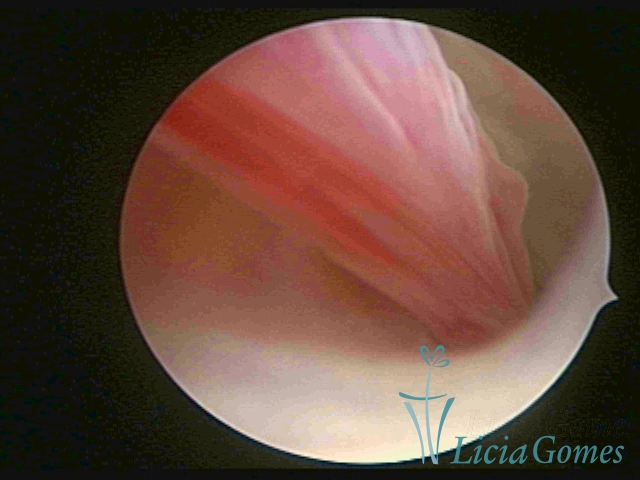

ENDOCERVICAL POLYPS

Benign tumors resulting from the reactive focal proliferation to inflammatory processes or hyperestrogenism situations, which may be sessile (with a large implantation) or stalked.